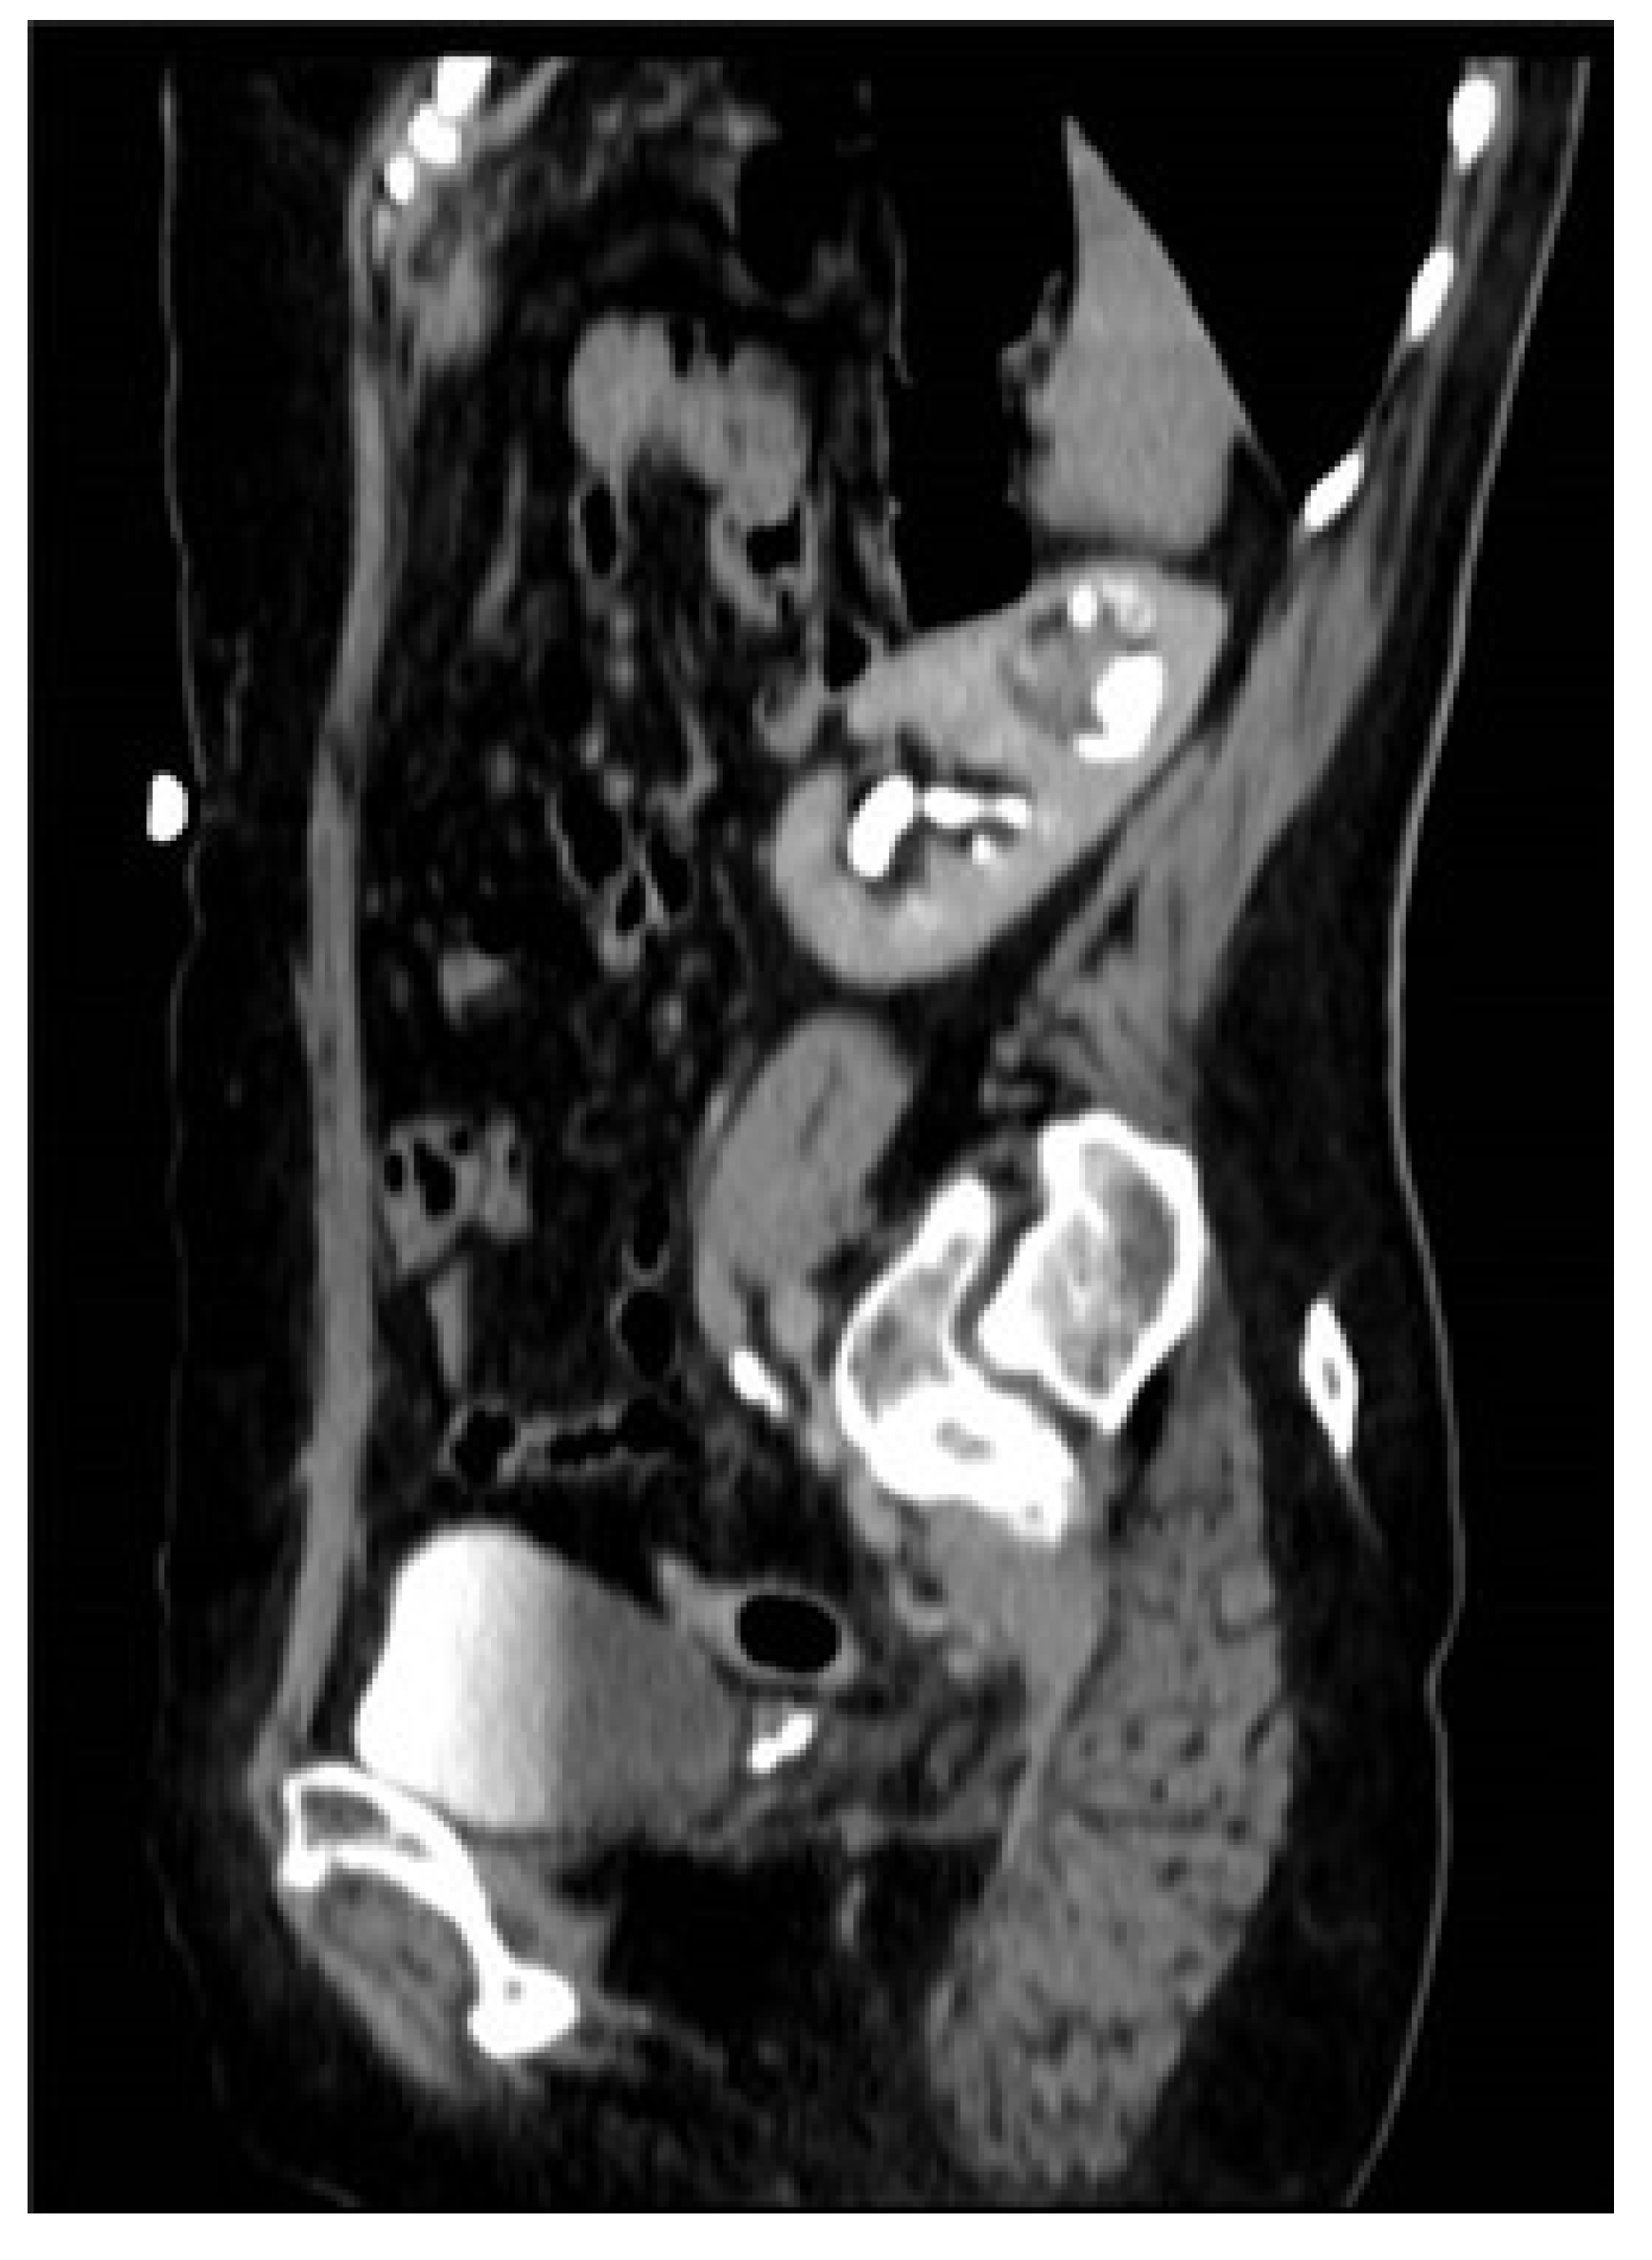

| 34 | Case presentation | 2023 | Israel | 69 | F | Hematuria | No per anamnesis | 0.8 | CTU, diagnostic URS | Complete | Left | Upper moiety renal pelvis | Upper pole Hemi-NU with distal common sheath ureterectomy, including bladder cuff, and reimplantation of the lower moiety ureter | Robotic assisted laparoscopic | Mucinous HG UC pT3NXM0 | Continued adjuvant therapy 9 months follow-up NED |